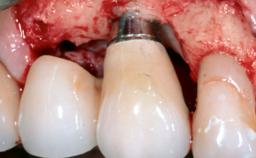

Reconstructive Surgical Treatment of Peri-Implantitis with Long-Term Follow-up

A 72-year-old female patient was referred to the specialist clinic with signs of peri-implantitis associated with implant 14. Two implants (sites 14 and 15) had been in function for three years. The patient was in good general health and was not taking any medication. She was a former smoker (12–15 cigarettes a day for 50 years) but had ceased smoking two years prior to implant placement. Her periodontal condition was stable, with no probing depths above 5 mm and a full-mouth plaque score (FMPS) of 35%.